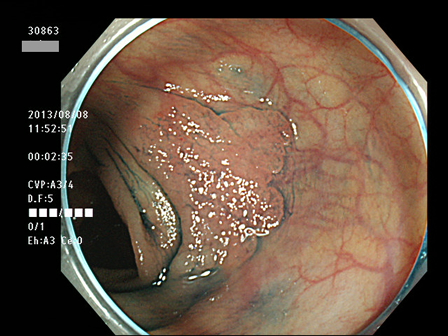

横行LST(平坦型腺腫)への注意

横行結腸の平坦型腺腫(LST)は「見落とし易い病変」の代表です

横行結腸はカーブしているため「接線方向からの観察」になり易く、LSTが認識しにくいのです

幸い、このタイプは癌化が「ゆっくり」なので「見落としが多い割には癌化は少ない」です